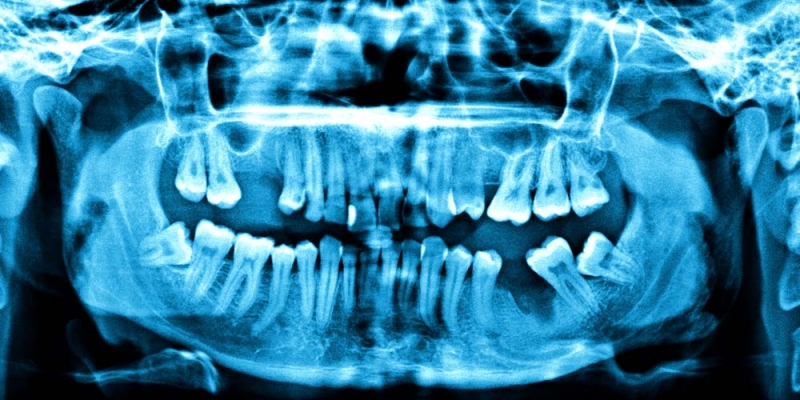

For years, dentists and the American Dental Association (ADA) have told us that we need yearly “bitewing” X-rays. They are required to find cavities that a visual exam might have overlooked, we are told.

Intracranial meningioma is the most common type of brain tumor. A study by the American Cancer Society found that tumor patients were twice as likely to have had bitewing X-rays as part of their regular dental regimen.

Another study looked at 188 women in California with intracranial meningiomas. It found that patients who started annual dental X-rays before they were 20 years old quadrupled their risk of developing brain tumors.

Here’s one other thing you need to know: Instead of standard X-rays, some dentists now offer something called cone-beam CT (CBCT). They promote it by saying it gives a more detailed view of your teeth. Your dentist may be aggressive in pushing this scan because he or she has to recoup the cost of the scanner.

But what they don’t tell you is that CBCT scans hit you with six times the radiation of bitewing X-rays.